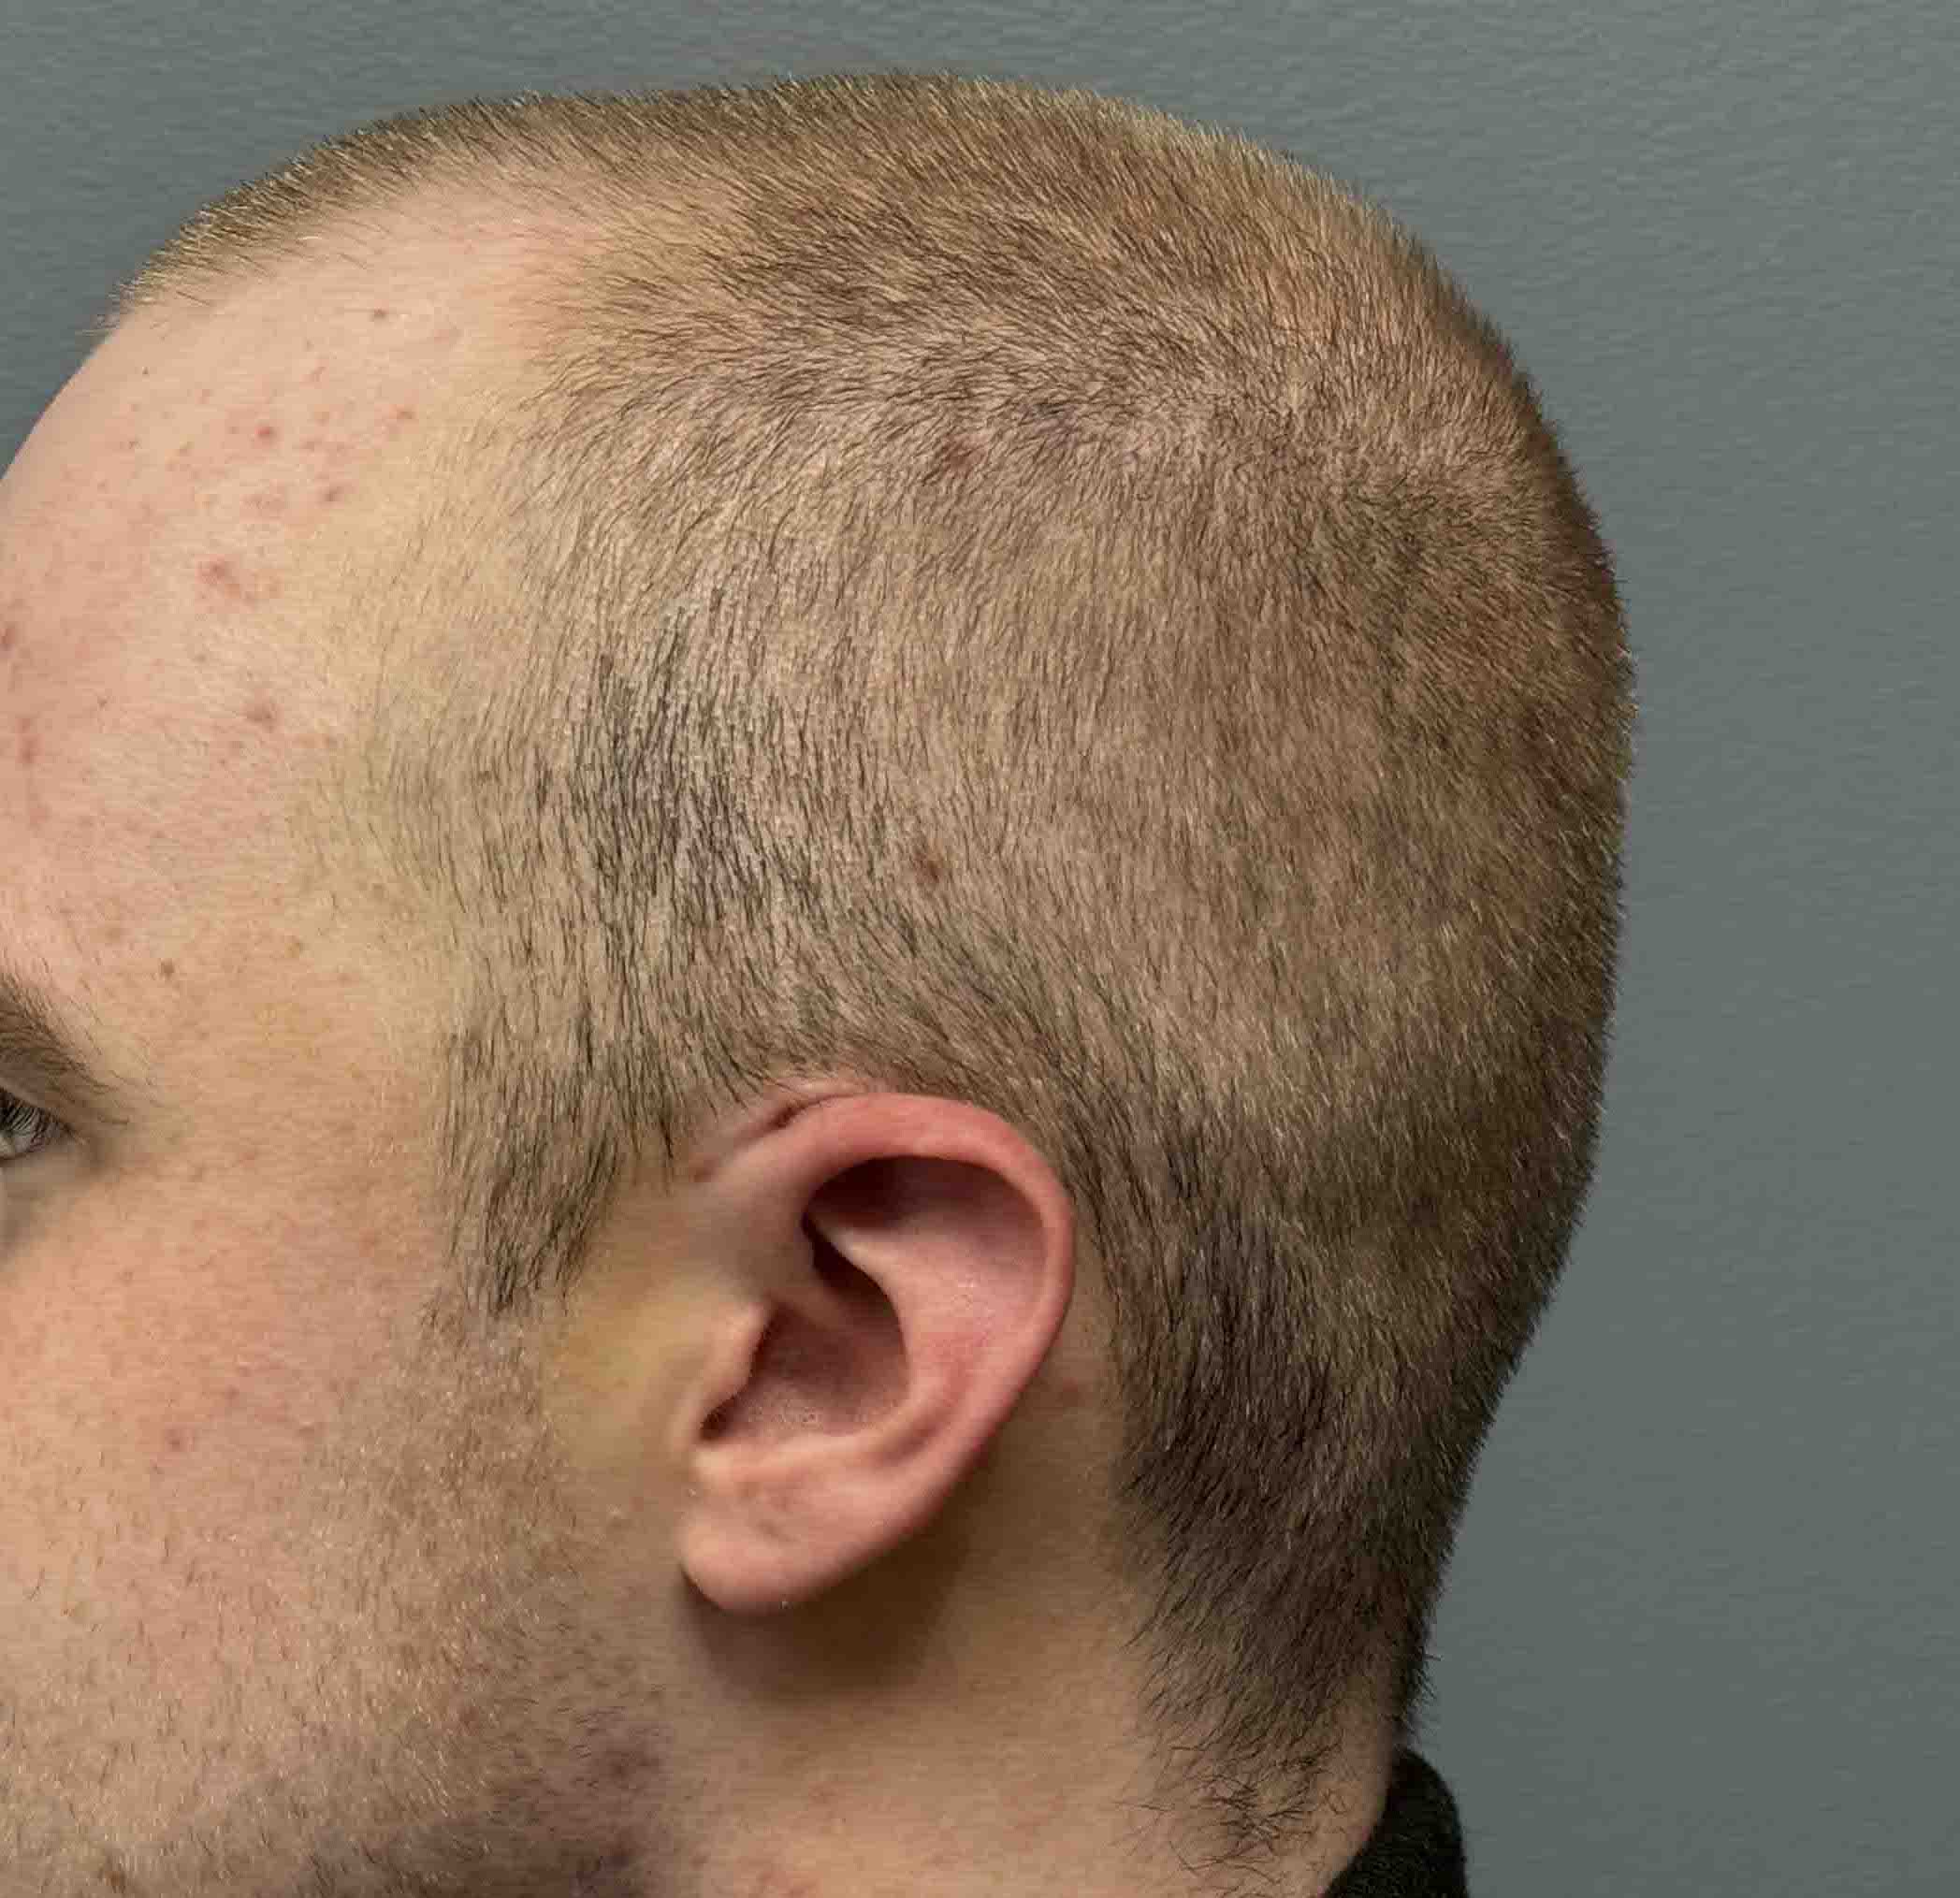

Patient 100

Desire for reshaping of an asymmetric flat back of the head in a shaved head male.

A combined back of the head reshaping procedure was done with a custom skull implant, sagittal ridge reduction and a right temporal muscle reduction.

Desire for reshaping of an asymmetric flat back of the head in a shaved head male.

A combined back of the head reshaping procedure was done with a custom skull implant, sagittal ridge reduction and a right temporal muscle reduction.